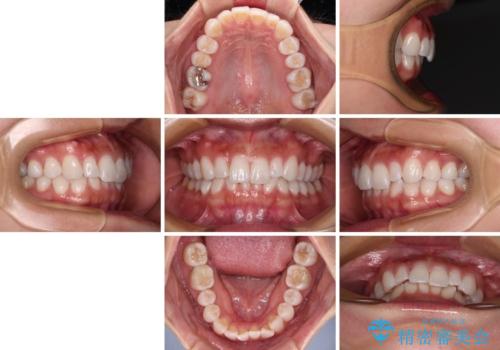

【モニター】前歯のデコボコと小さい前歯 インビザライン矯正とオールセラミッククラウン補綴治療

- 前歯の歯並びと生えてきたときから小さい前歯を気にして来院された患者様です。

上下前歯の歯列不正はインビザラインにより整え、その後に、矮小歯の前歯をオーダーメイドタイプのオールセラミッククラウンにて補綴治療することとしました。